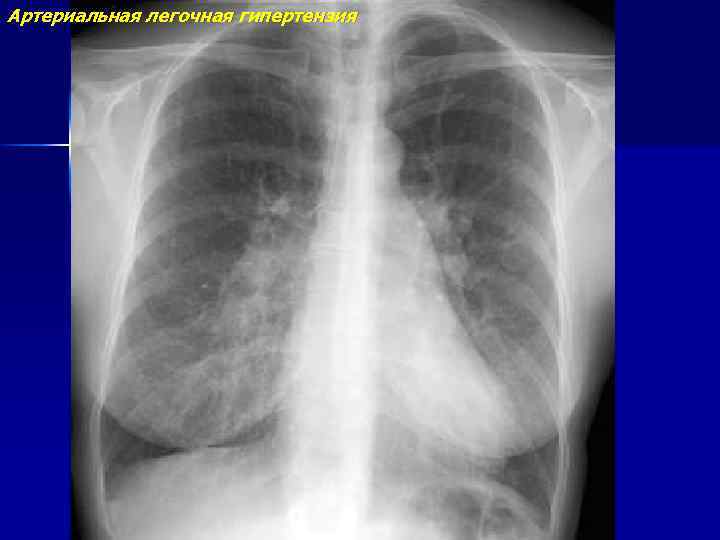

Артериальная легочная гипертензия